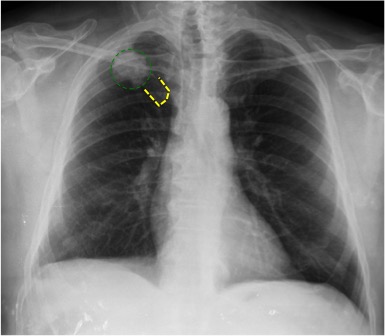

CASO: Febrícula y tos de 4 días de evolución.

Hallazgos:

- En la placa PA se observa una asimetría en los hilios pulmonares, el hilio izquierdo tiene una densidad aumentada.

- Tras examinar la placa lateral se observa un aumento de densidad en la columna que puede ser compatible con una condensación, es el signo de la desnificación vertebral.

SIGNO DE LA DENSIFICACIÓN VERTEBRAL: En la radiografía lateral normal, la densidad de la columna torácica tiende a disminuir desde la parte superior hasta el diafragma; la alteración de ese patrón por la presencia de una densidad superpuesta a la columna, indica la existencia de una consolidación pulmonar. Este signo adquiere especial valor cuando en la proyección posteroanterior la consolidación está oculta en el espacio retrocardíaco o en la base pulmonar.